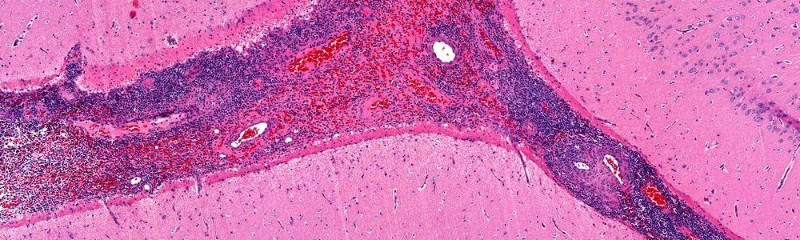

Геморагічний васкуліт (IgA-асоційований васкуліт, капіляротоксикоз, хвороба Шенлейна-Геноха, анафілактоїдна пурпура, атромбопенічна пурпура, тромбоцитопенічна пурпура) – це системне ураження капілярів, артеріол тощо, головним чином шкіри, суглобів, черевної порожнини та нирок. Ця хвороба відноситься до вікової групи 20-.

В основі захворювання лежить враження імунними комплексами стінок мікро судин, порушення мікроциркуляції, а також мікротромбози. Лікування даного захворювання відноситься до усунення запалень, укріплення судин, відновлення властивостей крові та профілактика мікротромбозів.